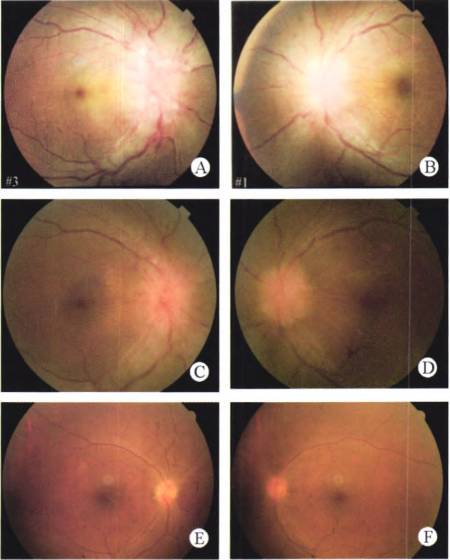

颅脑MRA显示:双侧颈内动脉岩段环形变细;颅脑MRV显示:左侧横窦较对侧细,近侧缺如,直窦代替横窦,上矢状窦直接与左横窦相连,考虑血管变异可能,右侧乙状窦及颈内静脉较对侧细(图5)

图5. 颅脑MRV左侧横窦较对侧细,近侧缺如,直窦代替横窦,上矢状窦直接与左横窦相连,右侧乙状窦及颈内静脉较对侧细